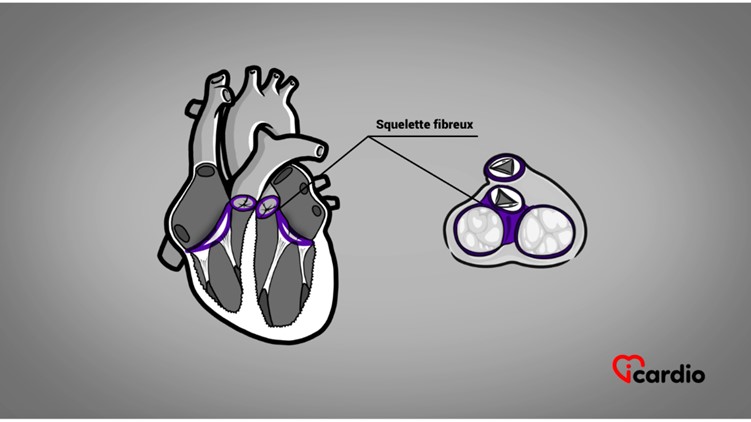

Le cœur est monté sur un squelette

Le cœur est monté sur un squelette fibreuxTout comme le corps humain, le cœur possède son squelette. Les 4 cavités et valves cardiaques y sont rattachées. >>, c’est-à-dire une structure rigide où il repose.

Les oreillettesLes oreillettes sont les deux cavités supérieures du cœur. Elles agissent comme des réservoirs du sang qui ira remplir les ventricules. >> et les ventriculesLes ventricules sont les 2 cavités inférieures du cœur. Ils sont plus musclés que les oreillettes; ils servent à propulser le sang pour assurer la circulation dans tout le corps. >> s’assemblent sur 2 gros anneaux qu’on appelle les anneaux auriculo-ventriculaires.

Les 2 autres anneaux sont plus petits. Ils rattachent l’artère pulmonaire au ventricule droit et l’aorte au ventricule gauche.